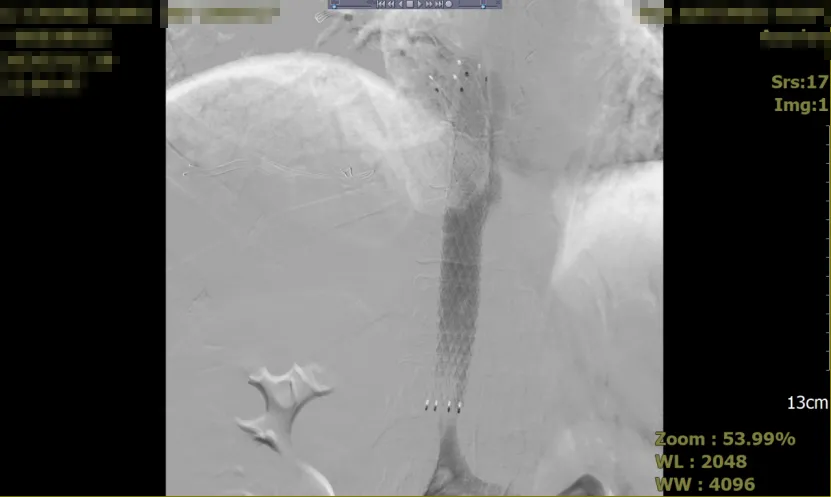

为防止血栓进一步迁移及加重症状,采取了介入治疗,具体措施包括:在2026年1月29日夜间,血栓取出,并植入支架以支撑血管通畅。

术后影像